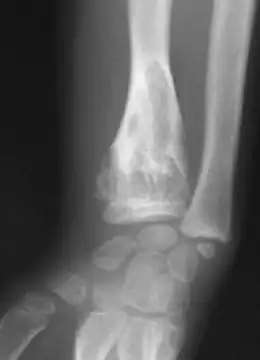

Exemple d'expression de la maladie d'Ollier, chez une fillette de 7 ans (radius)

Les premières manifestations de la maladie apparaissent en général durant la petite enfance du fait d'un développement perturbé de l'os par la croissance d'enchondromes multiples entraînant déformations, déviations axiales et différences de longueur entre les membres. Les tuméfactions osseuses se présentent radiologiquement comme des lacunes claires arrondies, finissant par se calcifier[7]. La pose du diagnostic se fait par un examen radiologique.